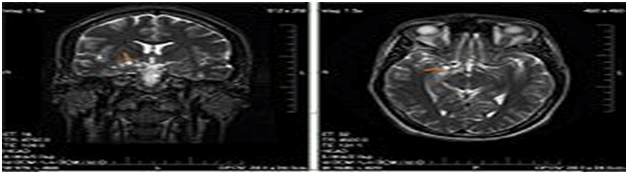

A glioma is a type of tumor that starts in the brain or spine. It is called a glioma because it arises from glial cells. The most common site of gliomas is the brain. Gliomas make up about 30% of all brain and central nervous system tumors and 80% of all malignant brain tumors (Figure 21).

Figure 21 CT scan of Glioma of the left parietal lobe (with contrast enhancement). According to WHO, glioma is classified by grades & locations. WHO grade <2 glioma are benign but incurable, recurrent, & progressively worse. WHO grade >2 Glioma are malign. The group comprises anaplastic astrocytoma’s and glioblastoma multiform. Whereas the median overall survival of anaplastic (WHO grade III) gliomas is approximately 3 years, glioblastoma multiformhas a poor median overall survival of ~15 months). Epigenetic repression of DNA repair, e.g. consuming diets high in nitrites and low in vitamin C, cell phone EM radiation(Wikipedia edited on 27 April 2017).